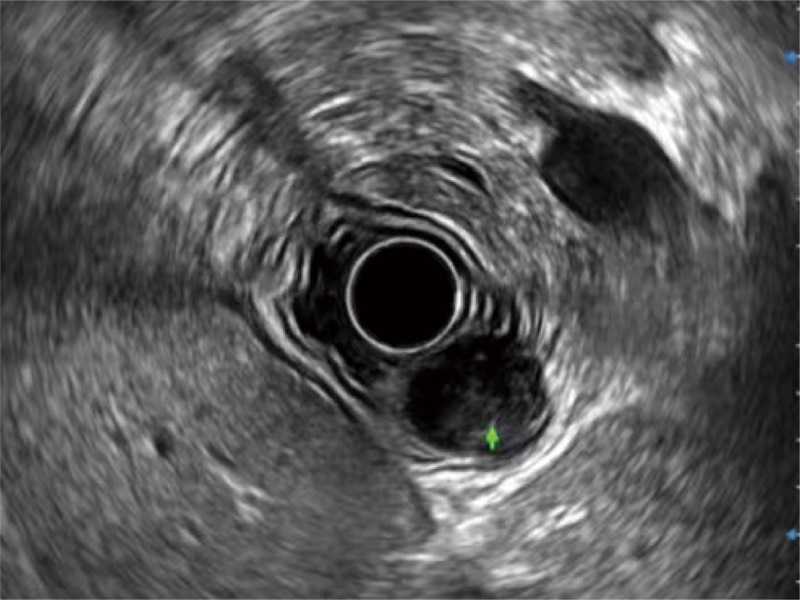

• 食管内间质瘤清晰显像

• 微米成像 (μ-Scan)

微米成像技术提升了对组织斑点噪声信号的抑制能力,并进一步强化边界信息,从而获得信噪比更优、边界更清楚锐利的图像